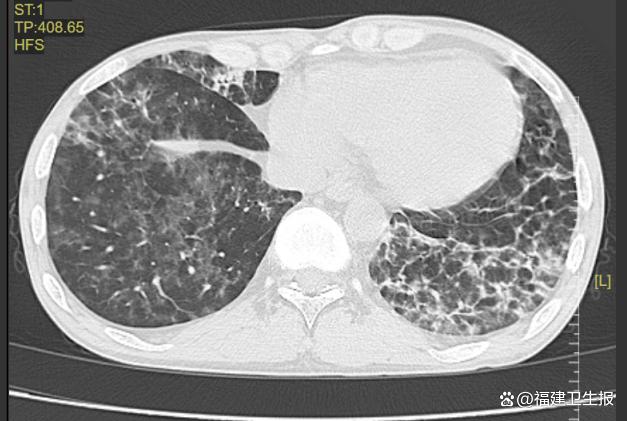

入院后的一系列检查很快揭示了令人震惊的事实:因为长期抗排斥治疗,导致钱先生的免疫力极低。更糟糕的是,淋巴细胞计数低下,炎症指标升高,胸部CT显示出肺部弥漫性斑片状、磨玻璃样的密度增高影,这是肺部感染的典型征象。

接诊的呼吸内科副主任医师林秀华通过支气管镜下肺泡灌洗术,最终锁定了背后的元凶:耶氏肺孢子菌肺炎。